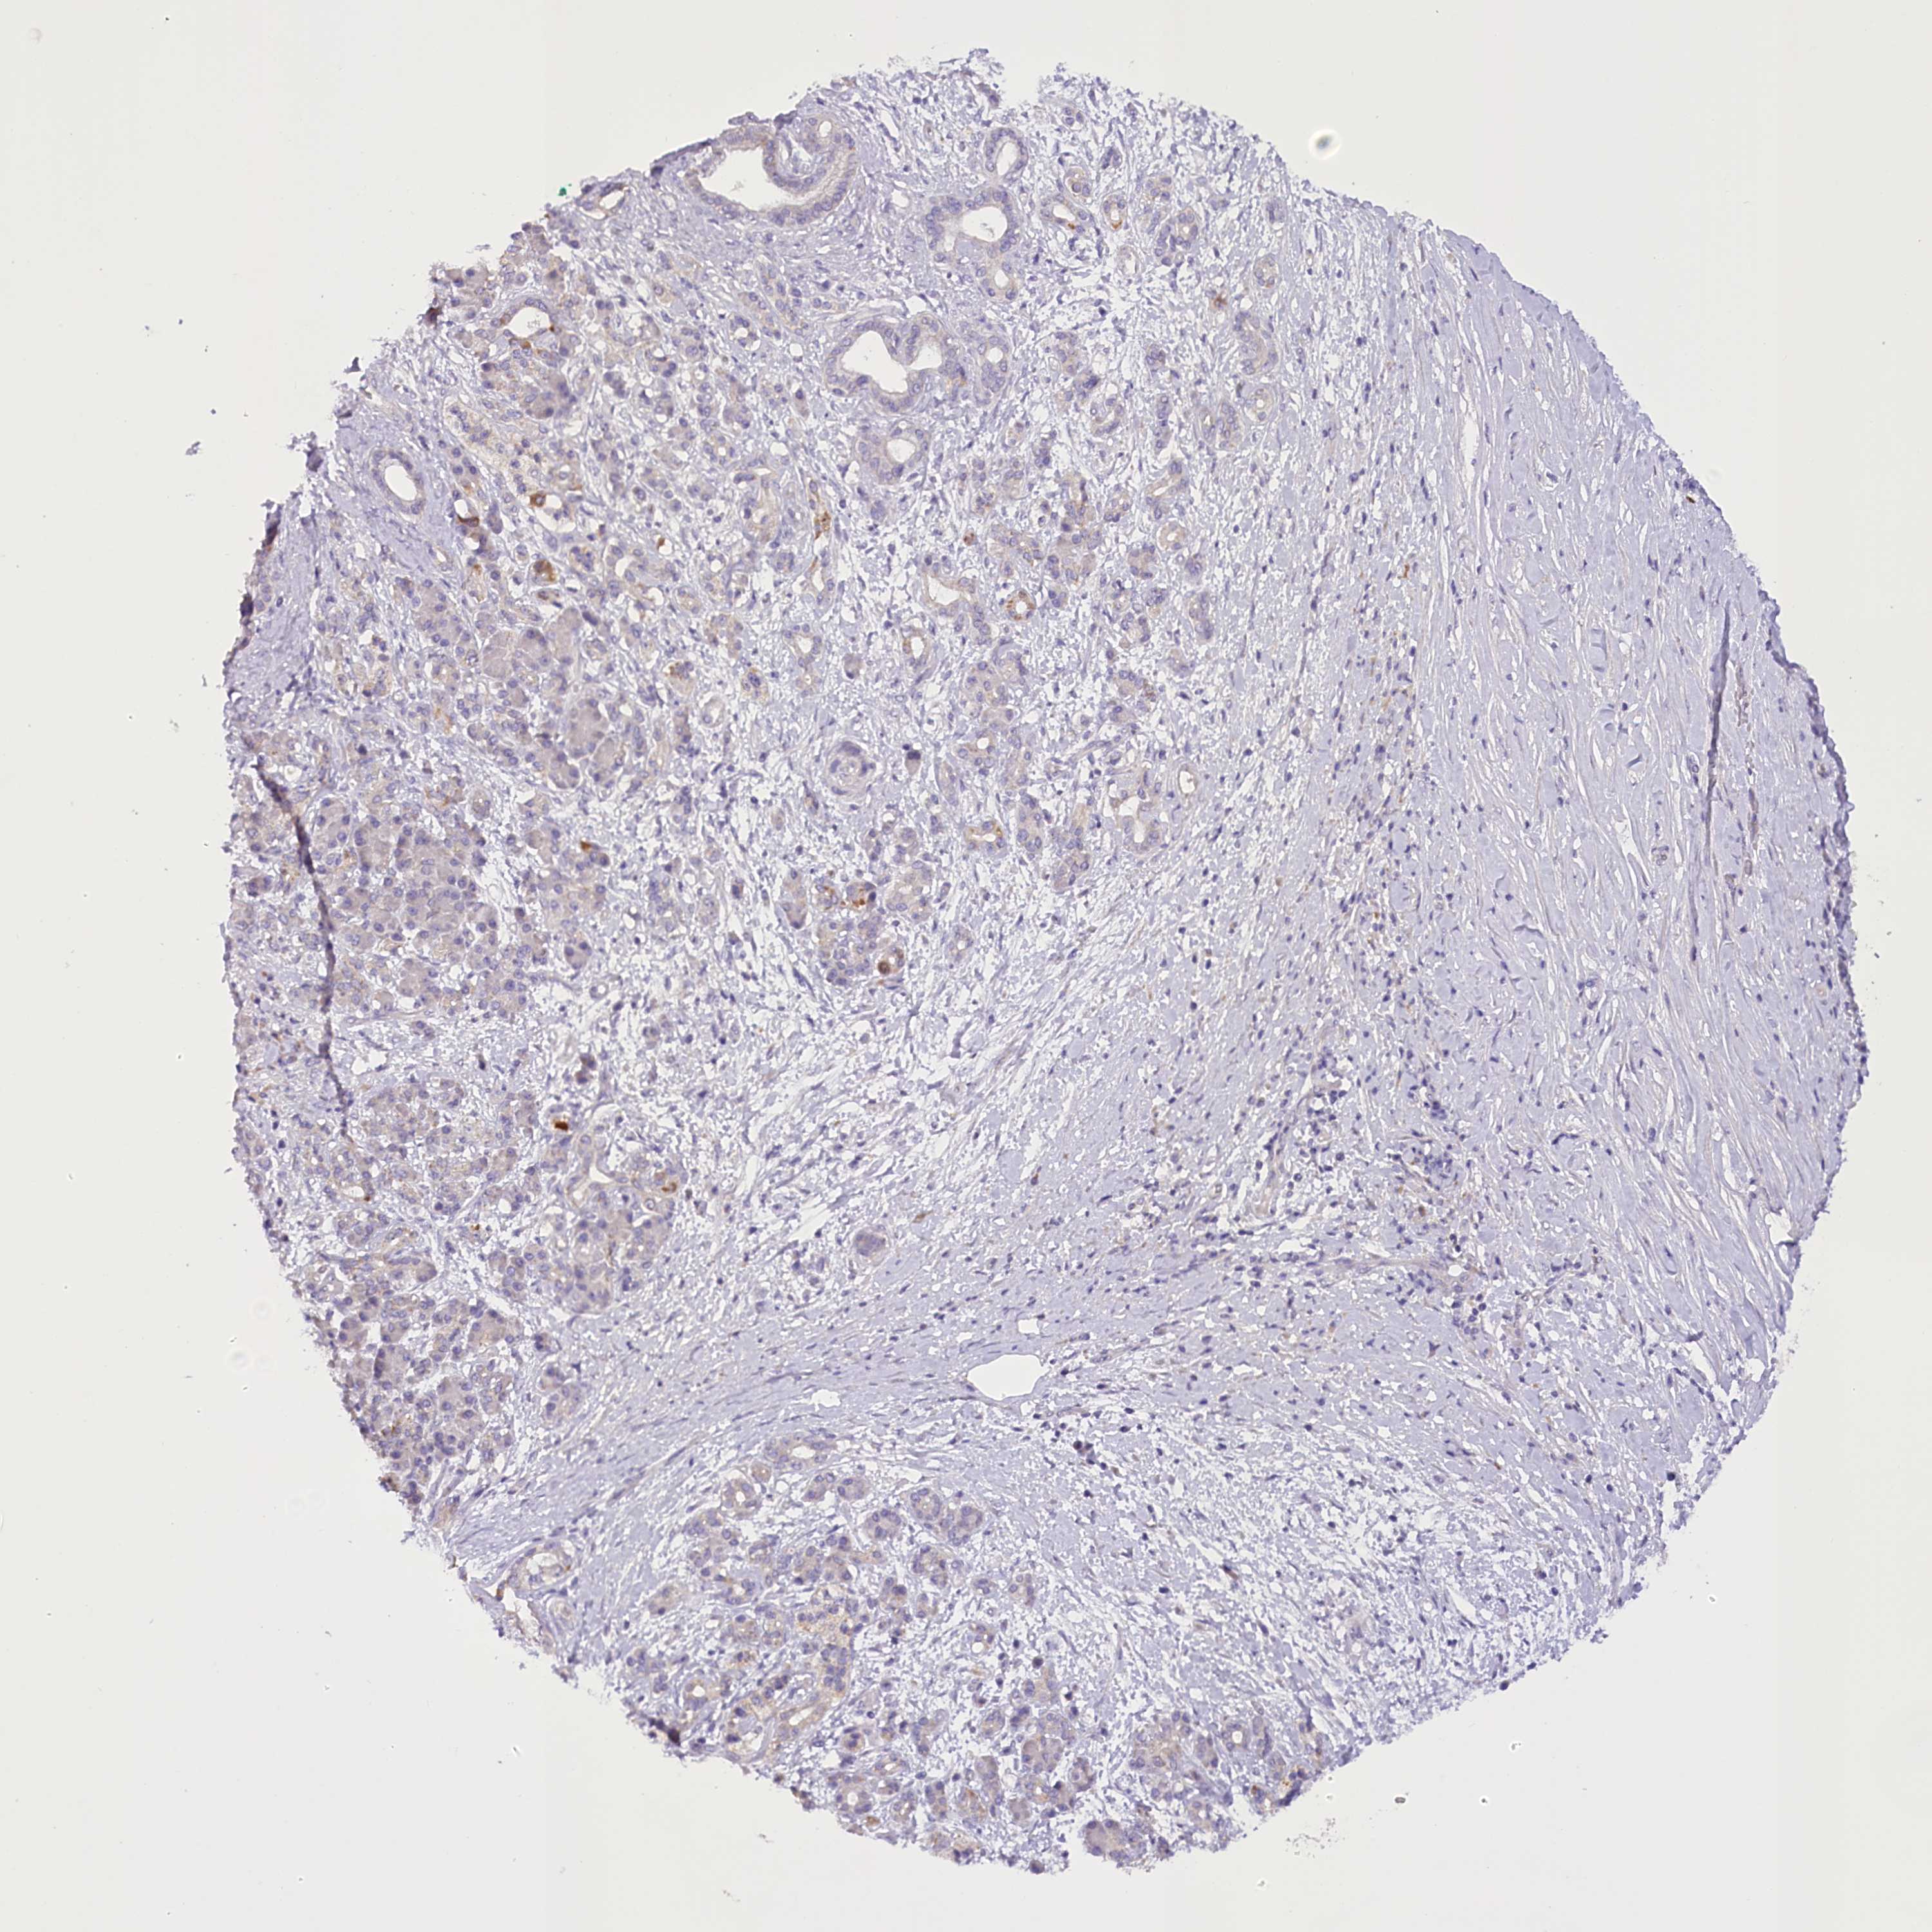

PANCREATIC CANCER - Protein expressioni

A mouse-over function shows sample information and annotation data. Click on an image to view it in a full screen mode. Samples can be filtered based on level of antibody staining by selecting one or several of the following categories: high, medium, low and not detected. The assay and annotation is described here.

Note that samples used for immunohistochemistry by the Human Protein Atlas do not correspond to samples in the TCGA dataset.

Antibody stainingi

Antibody staining in the annotated cell types in the current human tissue is reported as not detected, low, medium, or high, based on conventional immunohistochemistry profiling in selected tissues. This score is based on the combination of the staining intensity and fraction of stained cells.

Each image is clickable and will lead to virtual microscopy that enables deeper exploration of all samples and also displays staining intensity scores, fraction scores and subcellular localization as well as patient and tissue information for each sample.

Antibody HPA035911

Staining

High

Medium

Low

Not detected

Intensity

Strong

Moderate

Weak

Negative

Quantity

>75%

75%-25%

<25%

None

Location

Nuclear

Cytoplasmic/membranous

Cytoplasmic/membranous,nuclear

Adenocarcinoma, NOS